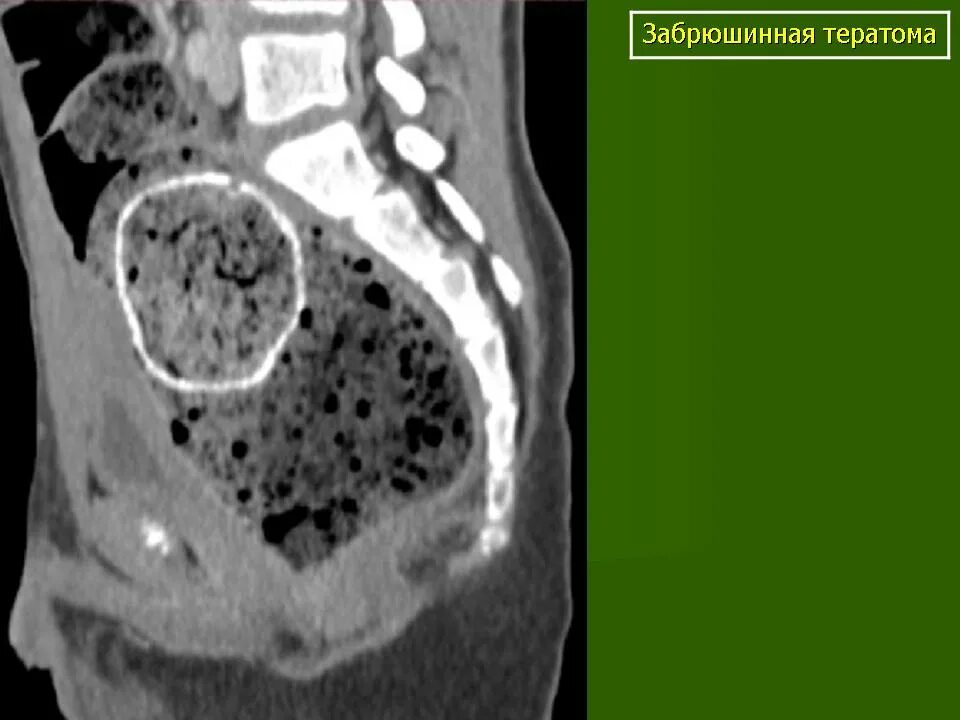

Забрюшинная онкология